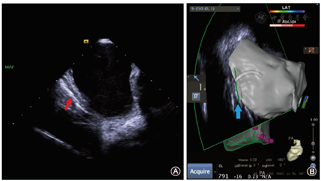

近年来,关于LAEF的预防已提出了一系列的措施。在术中,首先应当避免消融能量直接作用于食管。为实现这一点,Palaniswamy等[7]向食管中置入一根可塑性金属探针,并在消融术中使食管偏离消融径线,结果表明,该方法能够有效降低消融时食管内的温度,从而避免食管损伤。Arruda等[8]则设计出了一套食管内降温系统以减少消融能量对食管的热损伤,但目前还停留在动物试验阶段,尚未获临床研究验证。术中准确识别食管的位置及其与心房的关系也有助于预防食道损伤,如有学者提出将术前48 h的食道CT三维重建图像与三维电解剖标测技术结合用于术中食管定位[9]。心腔内超声的应用同样有助于判断消融位点与食管间的关系[10]。我中心在国内率先开展了心腔内超声引导下的房颤射频消融,该技术不但实现了消融过程零射线,也有助于术者更加精确地辨认左心房内的解剖结构,提高手术成功率。同时,该技术使术者可以实时监测消融导管、左心房后壁和食管之间的位置关系,有助于避免术中食管损伤(图5)。除了以上可能的保护性措施外,我们还应当注意,在后壁消融时,需要降低消融能量至25 W以下[2],随着消融指数(ablation index,AI)联合压力导管应用于临床实践,AI能够帮助我们更好地判断消融损伤程度。我中心总结经验后严格执行标准化的后壁消融策略,以期减少LAEF的发生风险:30 W功率模式下后壁消融时间<20 s,压力控制在15 g以内;AI指导的量化消融则需<350。但关于消融过程中如何选取最佳AI值以避免食管损伤仍需进一步的循证医学证据。关于术中食管内温度监测的应用目前尚存争议,一项研究比较了40例采用食管内温度监测与40例未采用温度监测的房颤射频消融患者术后内镜表现,多因素分析后发现温度监测是术后食管损伤的唯一独立危险因素。为除外金属探针与消融电极之间电热反应对食管的损伤,Halbfass等[11]采用了绝缘热电偶温度探测导管进行了相关研究,结果依然未发现温度监测对食管损伤的预防作用。